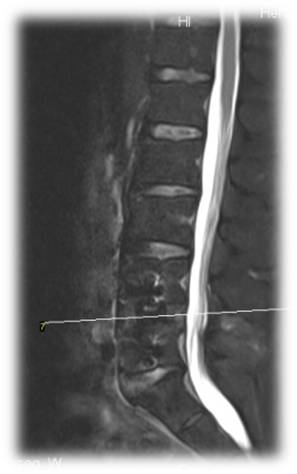

术前 图片1

术前 图片2

术前 图片3

术前 图片4

术前 图片5

术前 图片6